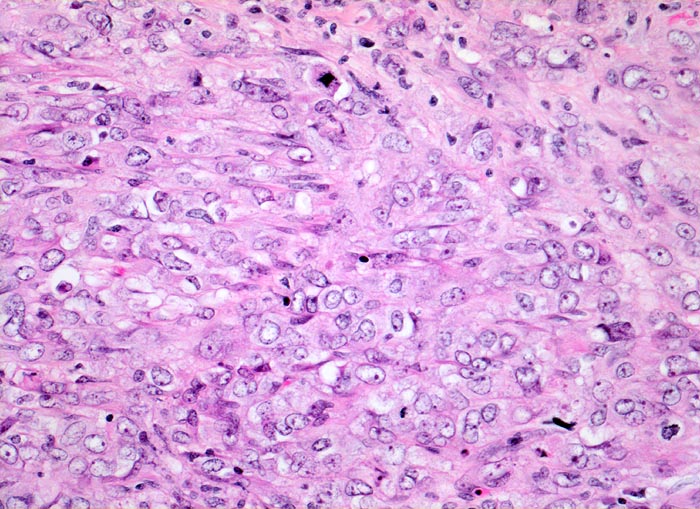

Morphologische Merkmale:

• Solider Tumor mit fokalen Entzündungsinfiltraten.

• Polymorphe Tumorzellen mit unscharfen Zellgrenzen und bläschenförmigen (=vesikulären) Kernen.

• Zahlreiche Mitosen.